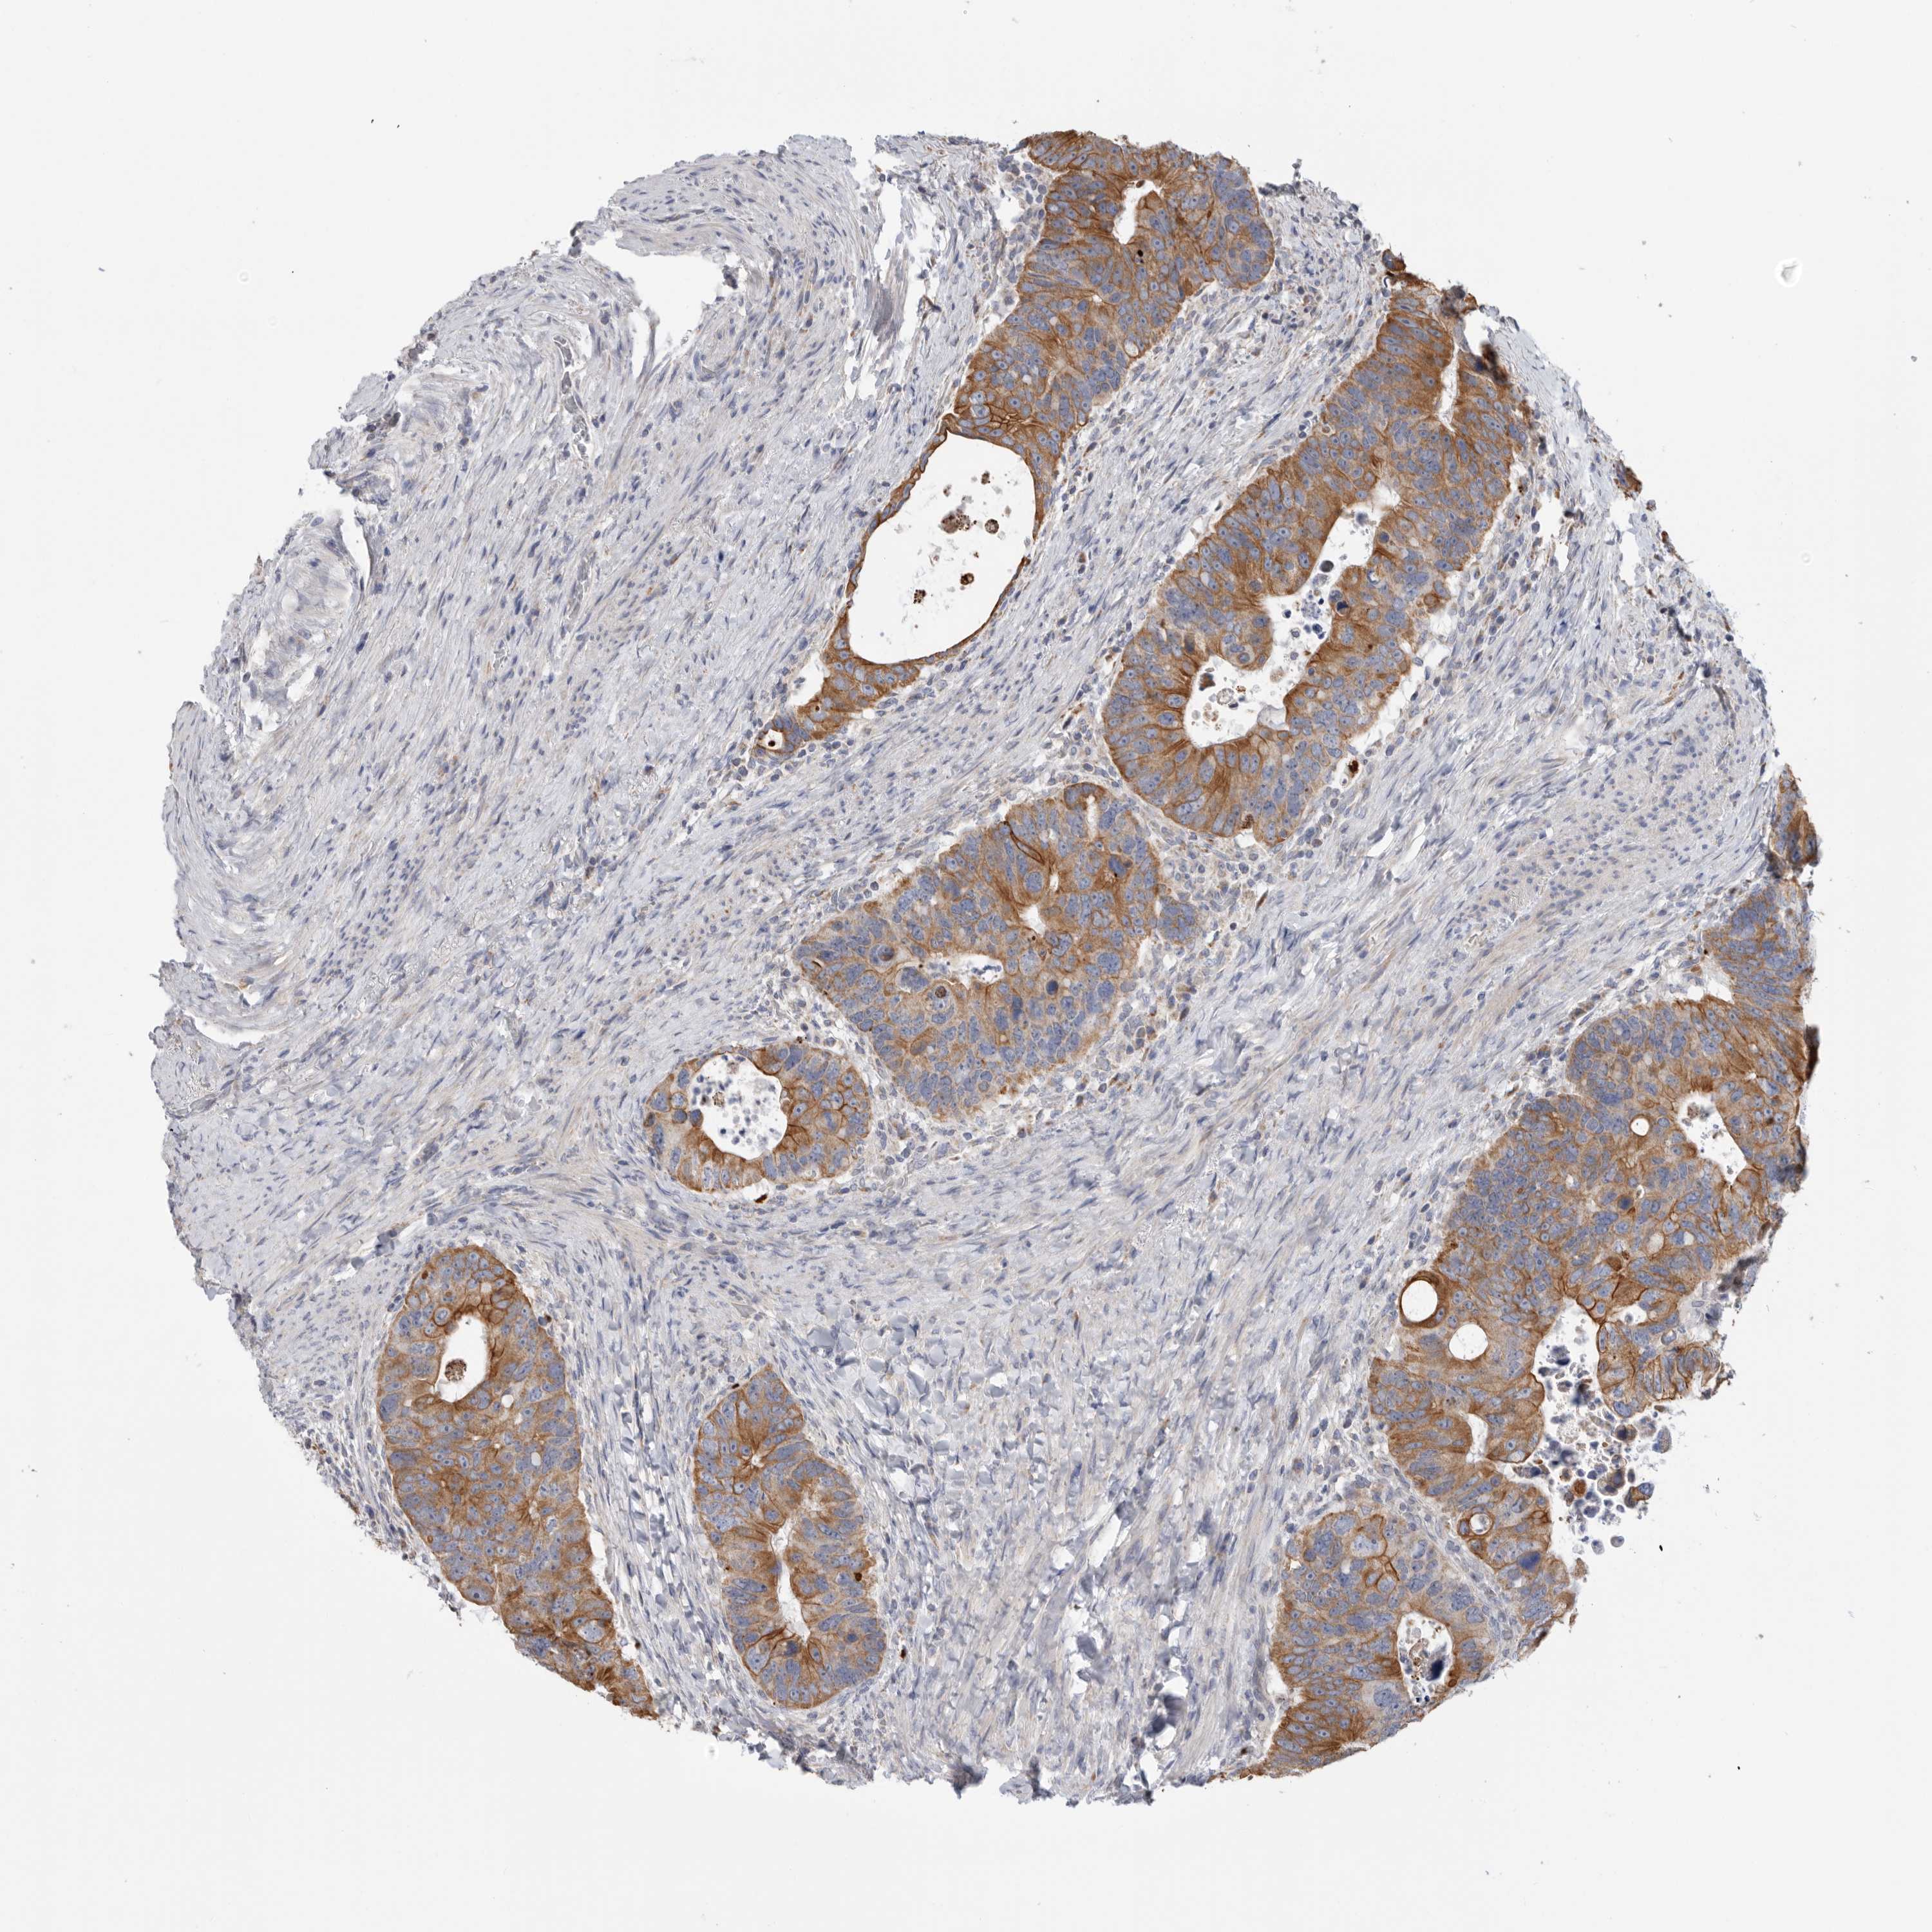

Colorectal cancer

Colon adenocarcinoma